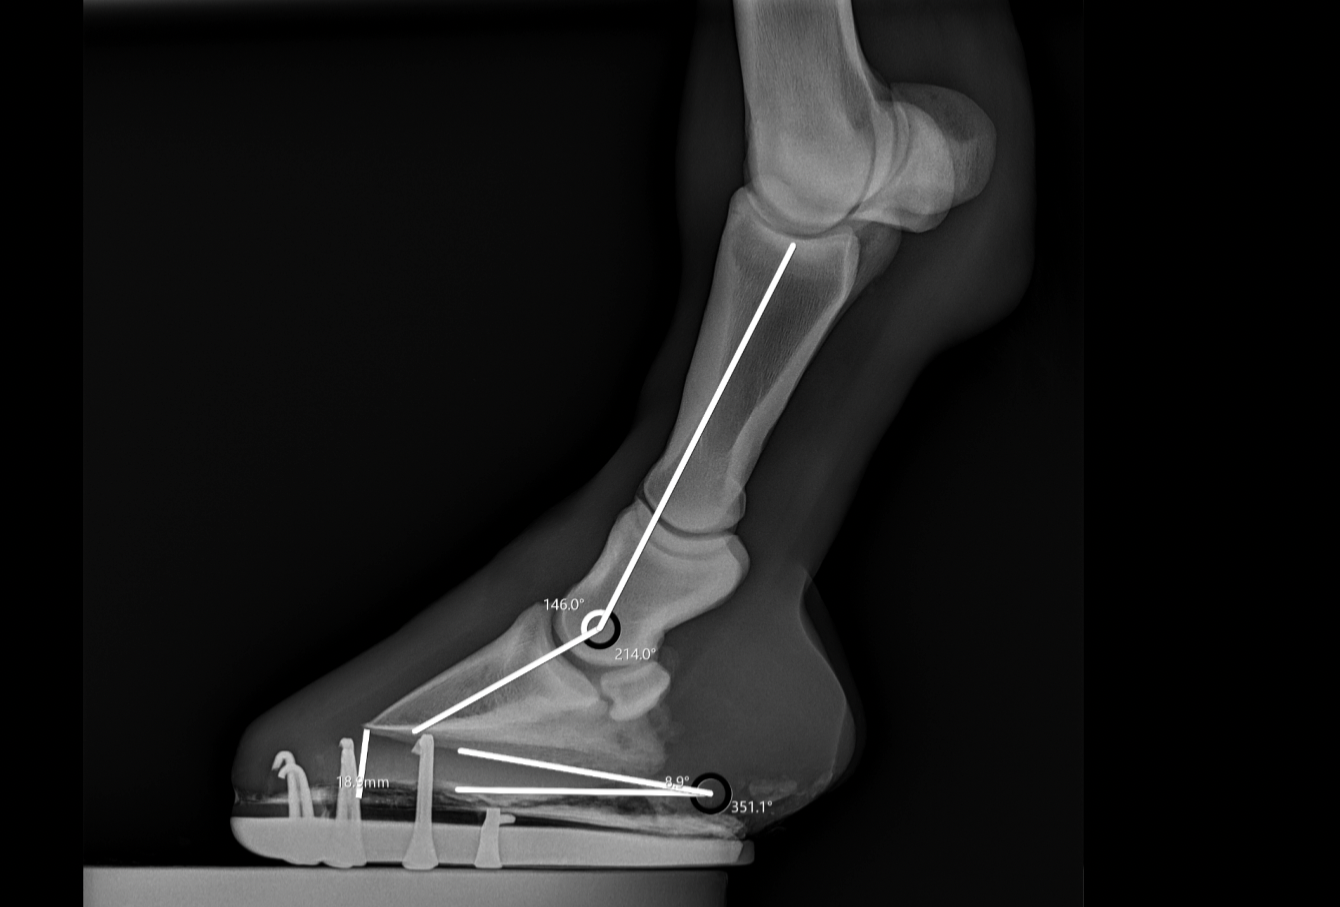

RADIOLOGIA ED ECOGRAFIA

Esami diagnostici avanzati per il benessere del tuo cavallo: radiologia ed ecografia per diagnosi precise e tempestive.

PODOLOGIA EQUINA

Gestione delle patologie del piede: Garantiscono una corretta postura, corretta locomozione e il benessere degli zoccoli e dell'animale in toto.